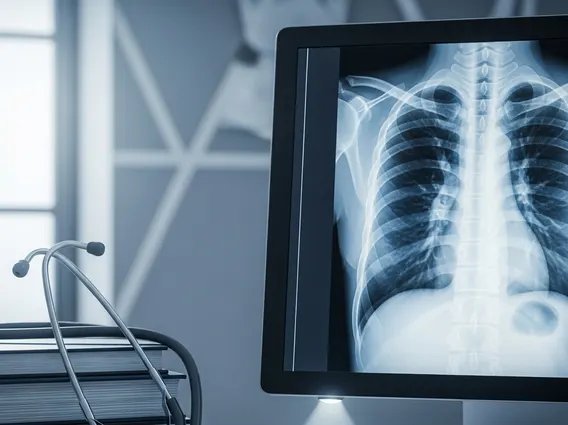

What is Respiratory Disease?

Respiratory Disease refers to any condition that affects the organs and tissues involved in breathing, such as the nasal passages, pharynx, larynx, trachea, bronchi, and lungs. These conditions can disrupt the normal exchange of oxygen and carbon dioxide, leading to symptoms like shortness of breath, coughing, and wheezing. Effective understanding respiratory health issues is vital, as these diseases are a major global health concern. According to the World Health Organization (WHO), chronic respiratory diseases are among the leading causes of death and disability worldwide, affecting hundreds of millions of people.